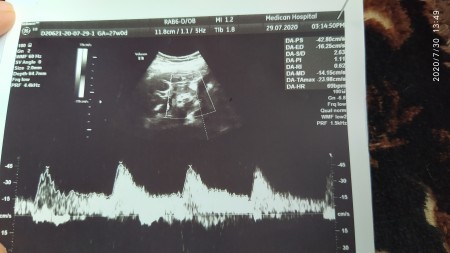

Dün detaylıya girdim, doktordan memnun kalmadım. Bebeğimin resmini bile doğru düzgün çekmedi :ermm: boyunu kilosunu da söylemedi. Bende o anki heycanla sormayı unuttum. Acaba burdan anlaşılır mı?

bu kalp atisi sadece canimm. Burda yazmaz

890grm 32.5 cmde boyu

Ac/bpd/fl falan yer var bu sekilde. Bak hemen onun karsisinda 890 yaziyor

görünmüyor Fl yazan yer boyu 7 ile çarp

Yaptım 32 çıktı, 26 haftaya göre normal mi canım?

güzel canm boyu